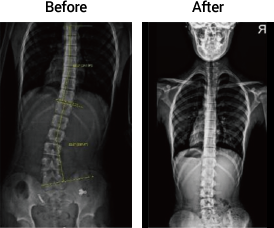

측만증

18세 여성

회전변형

18세 남성